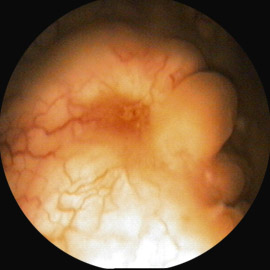

4. Метаплазия слизистой мочевого пузыря. Выполняется лазерная абляция слизистой.